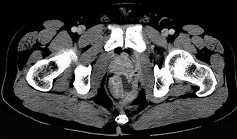

- 单项选择题男,28岁, 高热,肛门坠胀, 频有便意,直肠指诊时触及直肠粘膜下饱满, 柔软,压痛的肿块, CT检查如图,诊断为 ( )